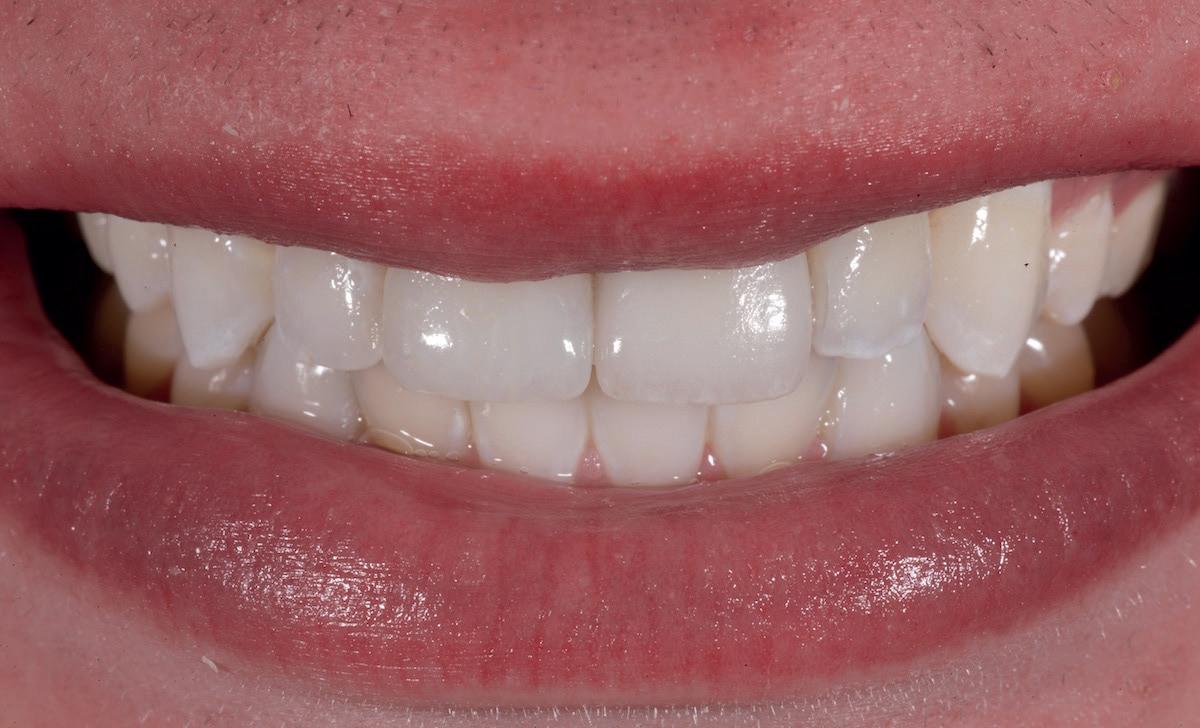

și „punte cu trei unități”, în prezent fiind la egalitate cu majoritatea sistemelor de titan. Deși datele pe termen lung nu au confirmat încă aceste rezultate bune, succesul de până acum este încurajator, astfel încât clinicienii profită de beneficiile clinice ale dioxidului de zirconiu în practica zilnică, introducând implanturile ceramice ca opțiune suplimentară în spectrul de opțiuni alături de cele de titan (fig. 1). Chiar

Posibilitatea ca nuanța gri să transpară prin gingie este un posibil dezavantaj al implanturilor de titan. În schimb, datorită culorii albe a dioxidului de zirconiu, această problemă estetică poate fi evitată prin

Totuși, ca și în cazul implanturilor de titan, în rare cazuri, și la cele ceramice poate apărea o recesie nedorită cu expunerea umărului implantar. Cu toate acestea, din punct de vedere estetic, această recesie a gingiei inflamate este posibil să fie mult mai bine tolerată de către pacienții preocupați de marginile întunecate ale implanturilor de titan (fig. 2).

În plus, aceste proprietăți bioinerte par să aibă și beneficii în ceea ce privește dezvoltarea periimplantitei și calitatea țesuturilor moi. În comparație cu titanul, dioxidul de zirconiu prezintă acumulare de placă și aderență bacteriană mai redusă, precum și o grosime mai mică a biofilmului depus. Și fluxul sanguin circulant către țesuturile moi este mai asemănător cu cel al unui dinte natural în cazul ceramicii față de titan, care oferă flux sanguin redus semnificativ. Se știe că o circulație sanguină mai bună înseamnă țesuturi moi mai sănătoase, care, la rândul lor, prezintă rezultate estetice îmbunătățite. Deși deocamdată lipsesc dovezile pe termen lung pentru implanturile ceramice, sunt disponibile rezultatele inițiale la 3 și 5 ani, iar tendința, susținută de studii preclinice și experiența clinică, este că dioxidul de zirconiu demonstrează același rezultat - iar în unele studii chiar o pierdere osoasă marginală mai redusă față de implanturile de titan. În această perioadă încă nu s-a descris clinic periimplantită.

1. Implanturi din titan (stânga) și zirconiu (dreapta). 2. Recesii la implanturile ceramice (stânga) și din titan (dreapta). 3. Țesut moale cu implant din zirconia, lipsit de inflamație.